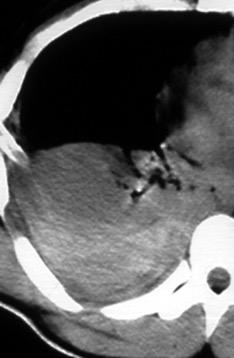

Signos radiológicos TC

Hallifax RJ et al. State-of-the-art: Radiological investigation of pleural disease Respiratory Medicine 2017

Nivel hidroaéreo o burbujas

Forma lenticular o elíptica Ángulos obtusos

> Grasa Extrapleural (60-80%)

Situación no gravitacional (no siempre)

Compresión de estructuras pulmonares

Límite muy bien definido Tabicación

Empiema